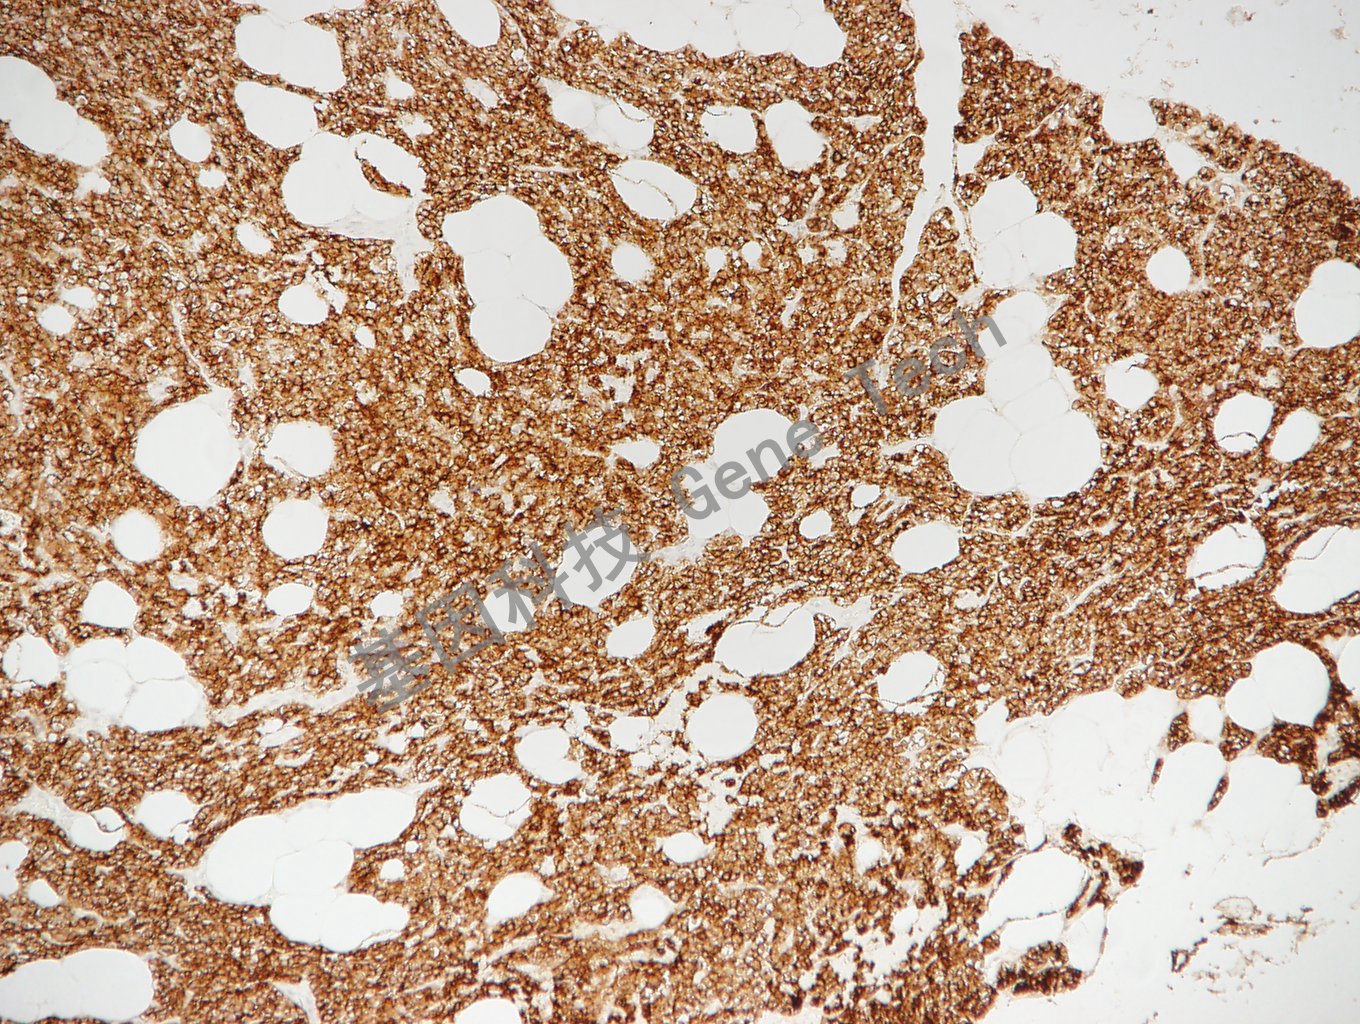

PTH 鼠抗人 PTH 甲状旁腺素 抗体试剂(免疫组织化学)

| 预处理:高pH热修复 | 阳性部位:细胞膜/细胞浆 | 阳性对照:甲状旁腺瘤 |

| 甲状旁腺瘤石蜡切片,用 PTH(GT2288)染色,细胞浆阳性,DAB显色。 | ||